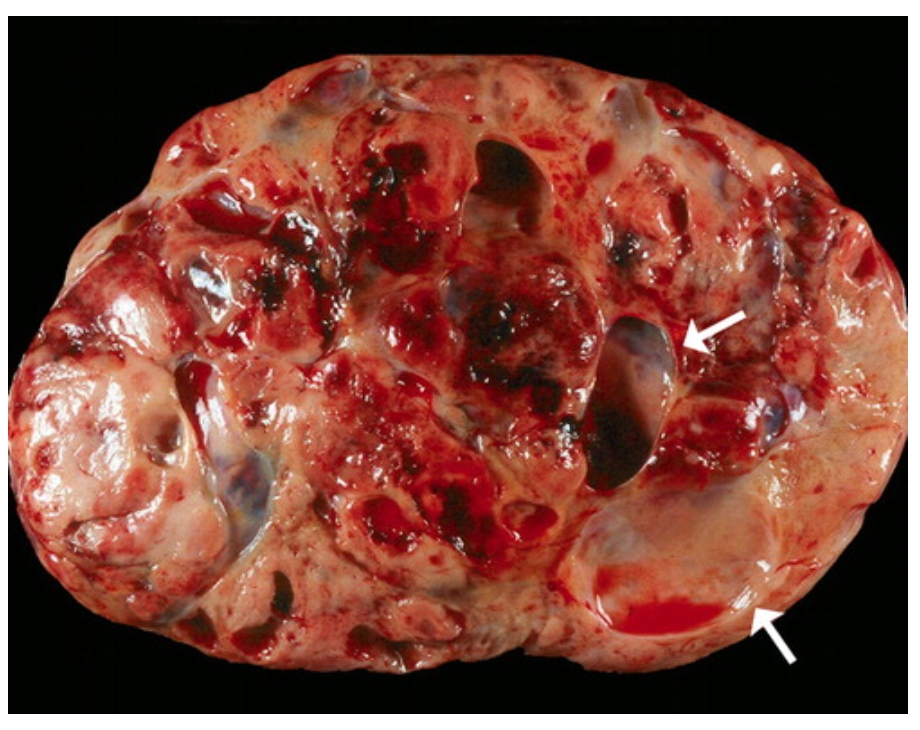

Pancreaticoblastoma

https://pubs.rsna.org/doi/10.1148/rg.264065012

Most common pancreatic tumour in children